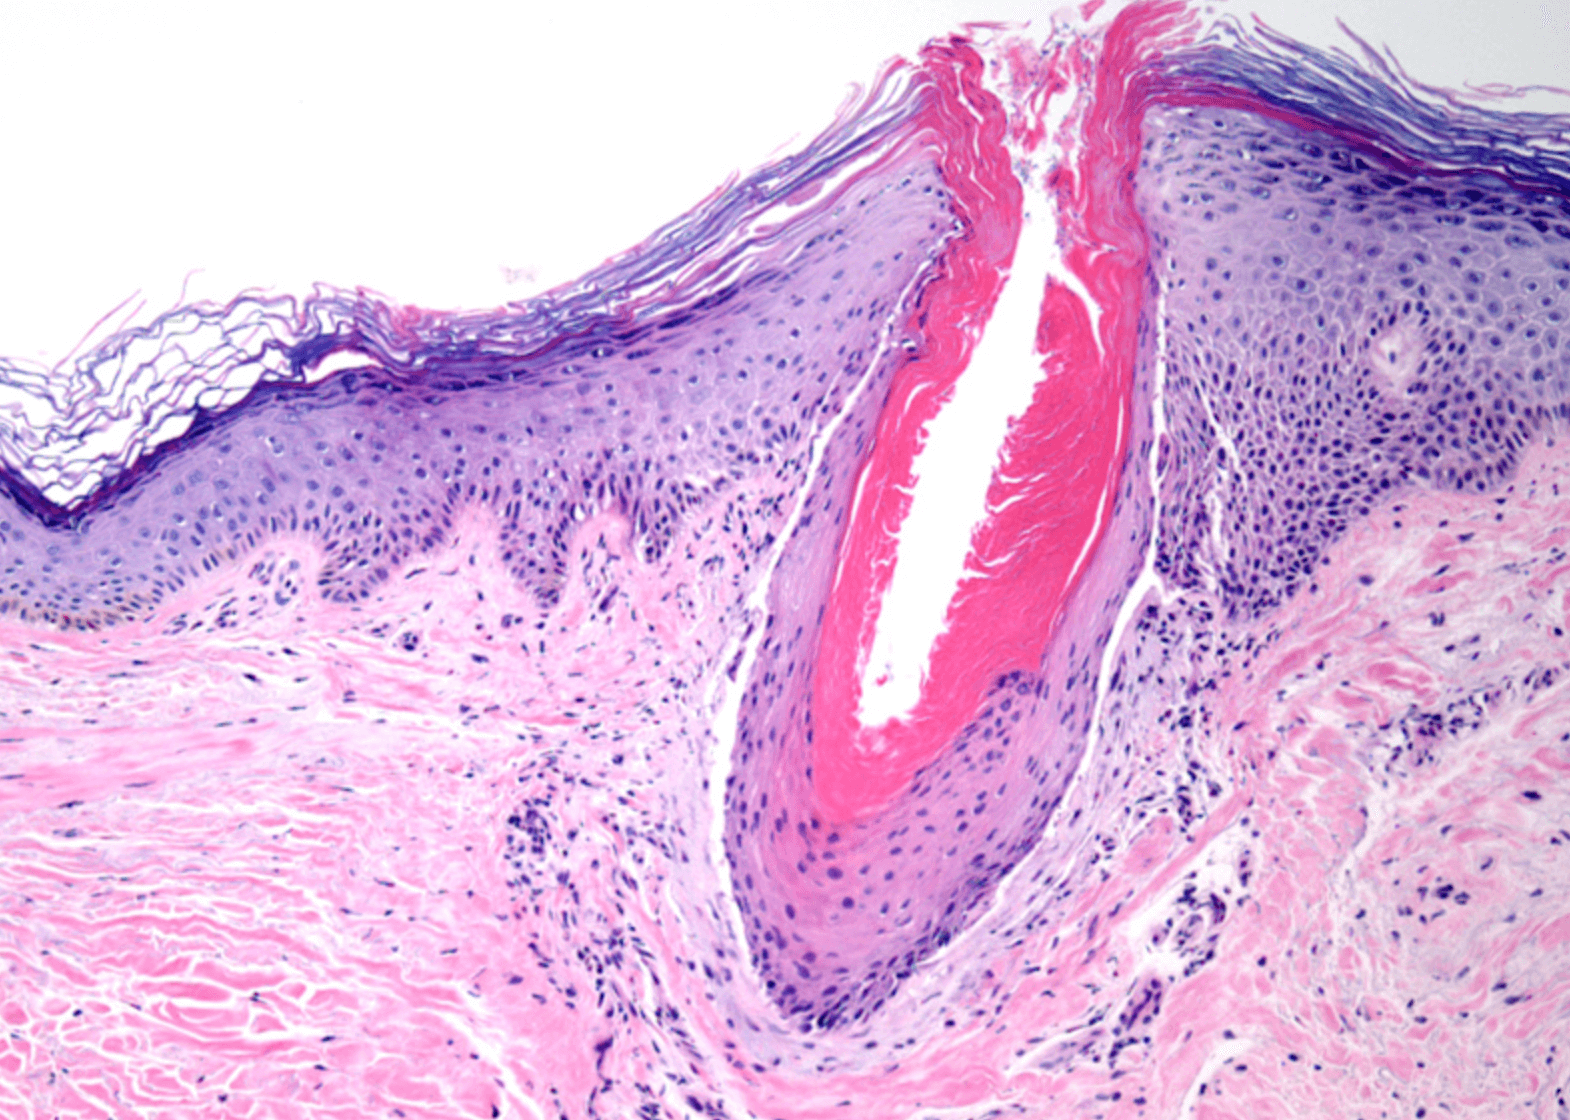

닭살돋은 느낌의 붉은 피부를 모공각화증 이라고 생각하시면 이해도가 쉬울것 같습니다. 이러한 작은 융기는 모낭을 막아 죽은 세포 이며, 보통 붉읂색 또는 갈색으로 나타납니다.

모공각화증은 유해 물질과 감염으로부터 피부를 보호하는 단단한 단백질인 케라틴이 축척되어 발생하며, 케라틴은 모낭의 열림을 막아 거칠고 오돌토돌한 피부를 만듭니다.